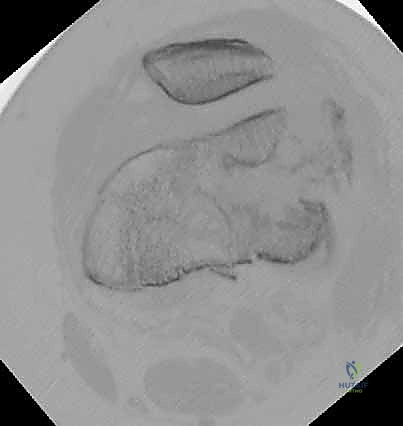

المرحلة الرابعة: التثبيت النهائي بالشرائح والمسامير (Fixation)

يتم استخدام "شرائح الإغلاق التشريحية" (Anatomical Locking Plates) المصنوعة من التيتانيوم عالي الجودة. هذه الشرائح مصممة خصيصاً لتأخذ شكل الجزء السفلي من عظم الفخذ. يتم تمرير الشريحة أسفل العضلات وتثبيتها بمسامير تغلق داخل الشريحة نفسها (Locking Screws)، مما يوفر ثباتاً ميكانيكياً هائلاً، حتى في حالات العظام الهشة.

في بعض الحالات المعقدة جداً، قد يتطلب الأمر استخدام شريحتين (Dual Plating) لضمان عدم تحرك الكسر أثناء فترة التعافي.